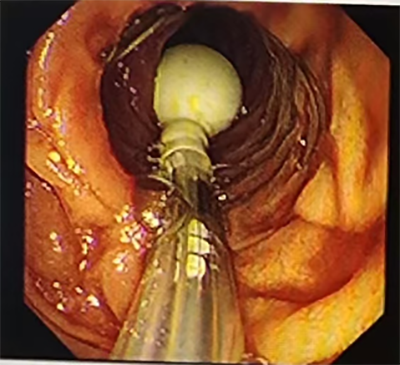

消化科副主任医师李涛副凭借丰富的消化介入经验,无需X线引导,将不需异物钳配合的经鼻超细胃镜经患者右侧鼻腔缓缓进入,抵达十二指肠远端。随后,通过活检通道送入导丝至门齿100cm,固定导丝后小心撤出超细胃镜,由助手丰丙程主治医师协助固定导丝,经导丝将肠梗阻导管顺利送达距门齿 90cm 处。为确保导管位置准确且功能正常,再经左侧鼻腔进超细胃镜至前球囊处,在直视下注入纯净水15ml观察到导管前端球囊扩张。随后撤镜、撤出导丝,局部体外固定导管。